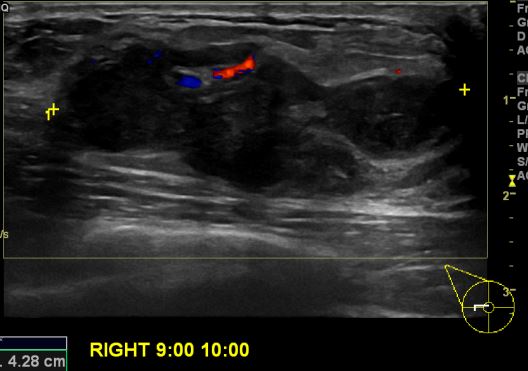

상기환자 우측 유방에 만져지는 멍울로 내원하신 40대 여성분으로 우측 9시에서10시

방향에 만져지는 멍울 조직검사 시행하여 우측 침윤성 유관암 진단 되었습니다.